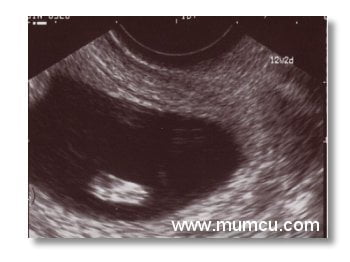

12 2/7 haftalık gebelikte bebeğin ayak tabanı

Vajinal ultrasonografi